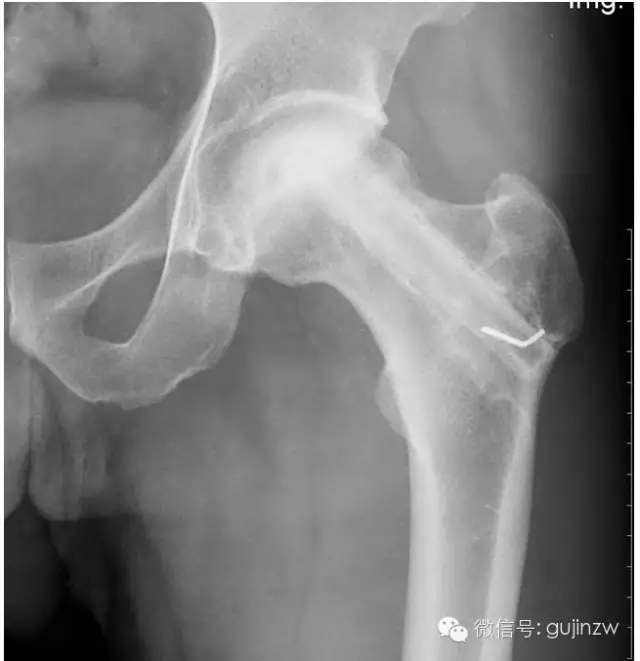

a、適應(yīng)癥:骨缺血性壞死、一般植骨術(shù)難以奏效時。

b、要點(diǎn):吻合血管,保存血運(yùn)